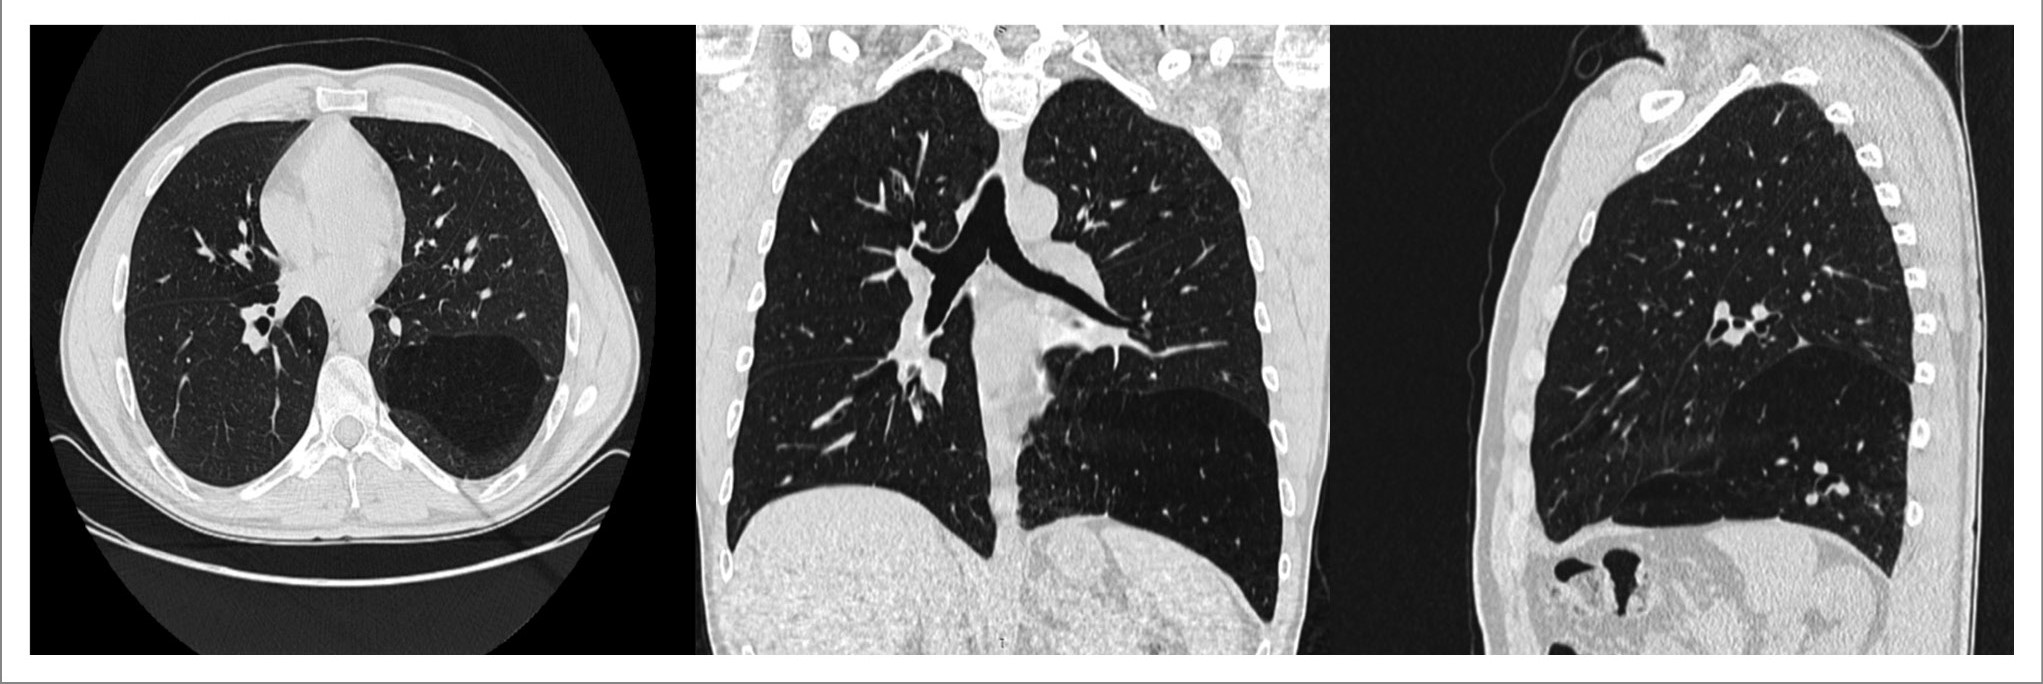

Мультиспиральная КТ (МСКТ) грудной клетки показала, что в заднебазальном отделе грудной клетки слева определяется чрезмерно вздутый участок легочной ткани пирамидальной формы (образование) полностью прилегающий к диафрагме, частично по передней и заднебоковой поверхности грудной клетки, размерами 14×14×11 см (на вдохе) с эмфизематозными изменениями (симптом «воздушной ловушки»), отделенный листком плевры от функционирующей легочной ткани левого легкого. Связь с бронхиальным деревом не прослеживается. Плотность образования на вдохе – 972–985 HU, на выдохе – 926–945 HU. Средостение и трахея смещены вправо. Левое легкое поджато кверху, легочный рисунок в данном участке прослеживается, ткань воздушна (рис. 2).

Рис. 2. МСКТ ОГК (нативное исследование): в заднебазальном отделе грудной клетки слева определяется участок (образование) легочной ткани пирамидальной формы, полностью прилегающий к диафрагме, отделенный листком плевры от остальной функционирующей легочной ткани, не меняющий своей воздушности на вдохе и на выдохе – симптом «воздушной ловушки».